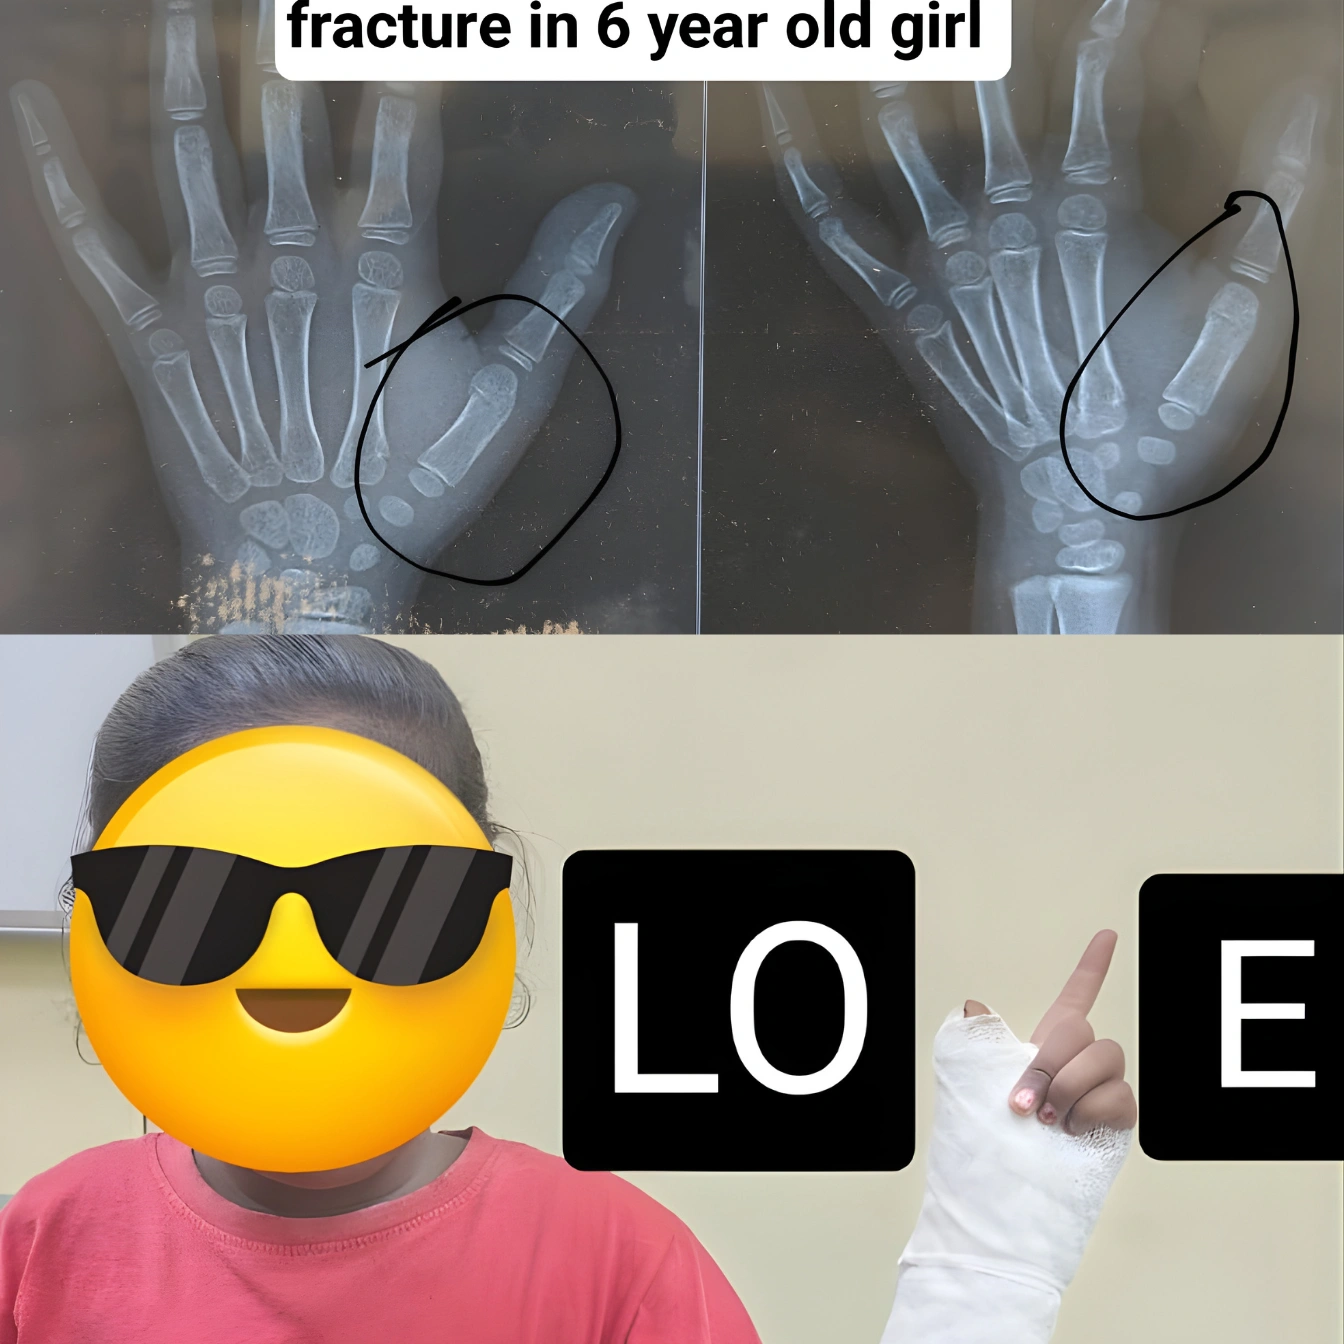

Professional Orthopedic Care for Bones, Joints and Spine

Supporting healthy bones, joints and spine with care that reduces pain and improves everyday movement, helping individuals stay active and mobile.